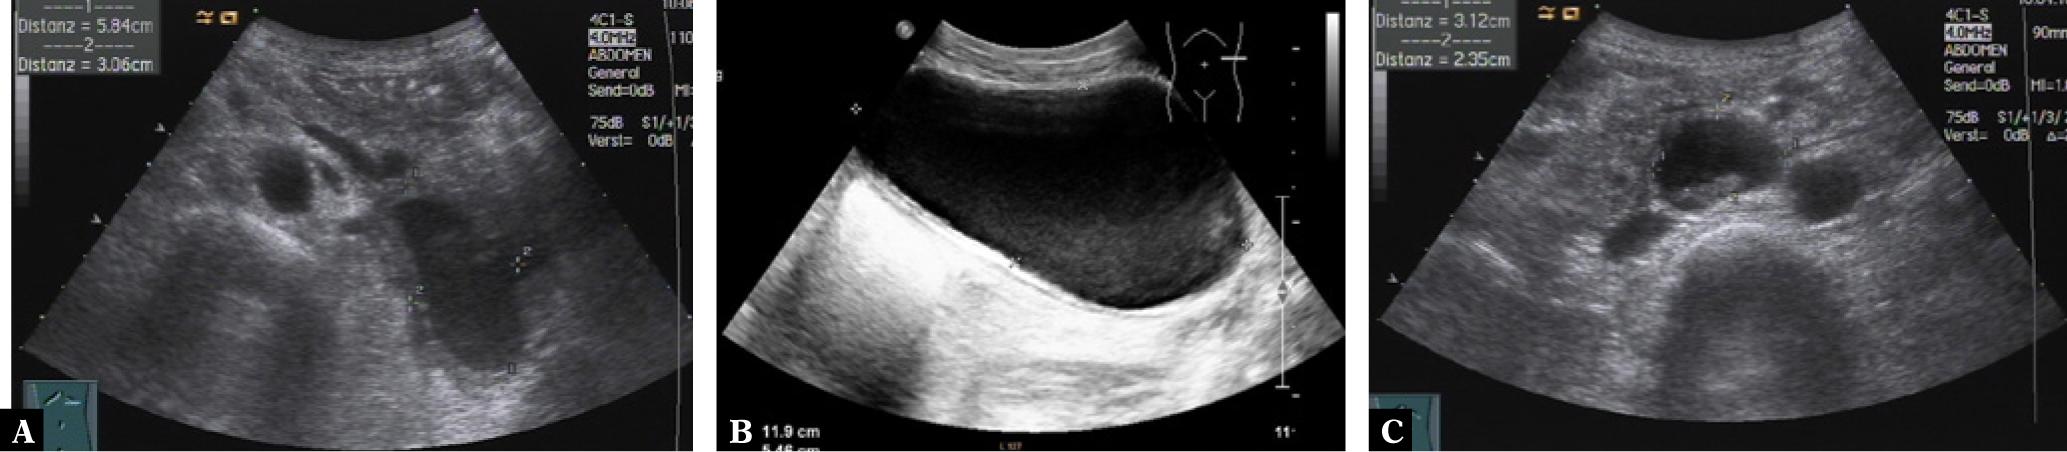

Pancreatic and retroperitoneal endometriosis mimicking pancreatic pseudocyst is presented by the second image sequence. A 40-year old woman presented in March 2015 with diffuse abdominal pain, nausea and weight loss. Medical history included active alcohol abuse and uterine rupture during pregnancy five years before. Ultrasound (Fig. 5) and computed tomography (Fig. 6) revealed multiple confluent cystic lesions with a thick cystic wall in the left abdomen with contact to the pancreatic tail suggestive of pancreatic pseudocysts. However, neither ultrasound nor CT revealed abnormalities of the pancreatic parenchyma or the pancreatic duct. A further cystic lesion was detected in the retroperitoneum between the abdominal aorta and the inferior caval vein. Percutaneous ultrasound guided aspiration of the cystic fluid and biopsy of the cystic wall were performed to rule out malignancy. Analysis of the chocolate-like fluid revealed a markedly increased lipase concentration (13.697 U/L), supporting the diagnosis of pancreatic pseudocysts. Histological examination, however, resulted in the diagnosis of pancreatic endometriosis. This diagnosis was confirmed after surgical resection and pathological analysis of the surgical specimen.

Transabdominal ultrasound of a pancreatic and retroperitoneal endometriosis mimicking pancreatic pseudocysts. Left upper abdominal oblique scan showing a large cystic lesion with slightly echogenic content, thick cystic wall and contact to the pancreatic tail (A). Left flank scan demonstrating a large cystic lesion with echogenic sediment and a thick cystic wall with several layers (B). Transverse abdominal scan revealing a mixed cystic solid lesion with a thick wall between the abdominal aorta and the inferior caval vein (C)